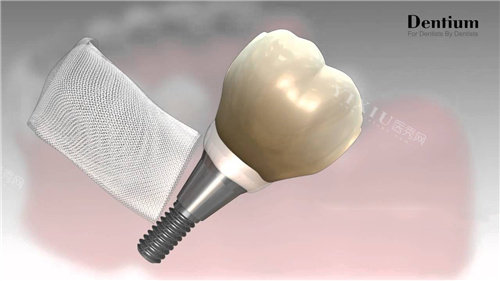

四级纯钛材质:登腾采用生物相容性较好的四级纯钛,表面经S.L.A大颗粒喷砂酸蚀处理,形成微观多孔结构,骨细胞黏附效率提升40%。

内八角锥形设计:植体与牙槽骨接触面积增加25%,初期稳定性提升30%。临床数据显示,在D2类中等密度骨质中,登腾种植体3周骨整合率达92%,远超行业平均80%标准。

美学需求:登腾提供全瓷冠定制服务,颜色、形态、光泽度可与邻牙高度匹配,满足年轻人对自然美观的追求。